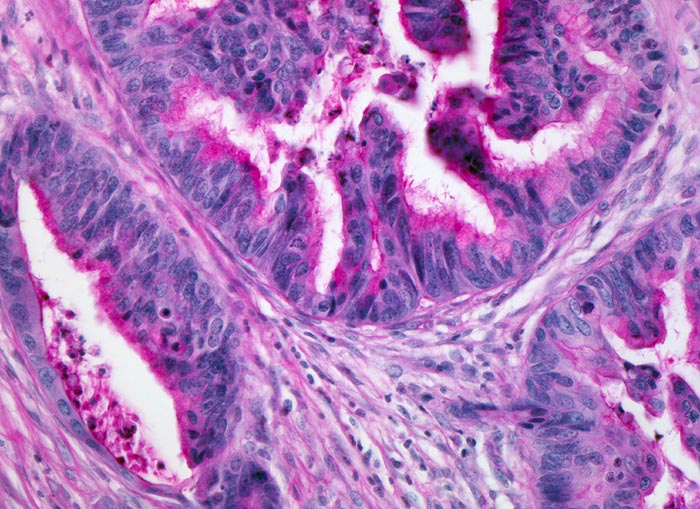

• Die Karzinomdrüsen sind unregelmässig verzweigt und bilden teils kribriforme Strukturen.

• Ektatische Tumordrüsen sind gefüllt mit nekrotischem Zelldetritus.

• Sich gegenseitig überlagernde, abgerundete, vergrösserte und hyperchromatische Tumorzellkerne.

• Stark verminderte Schleimbildung in den Tumorzellen. Das sollte der Kliniker dem Pathologen mitteilen: